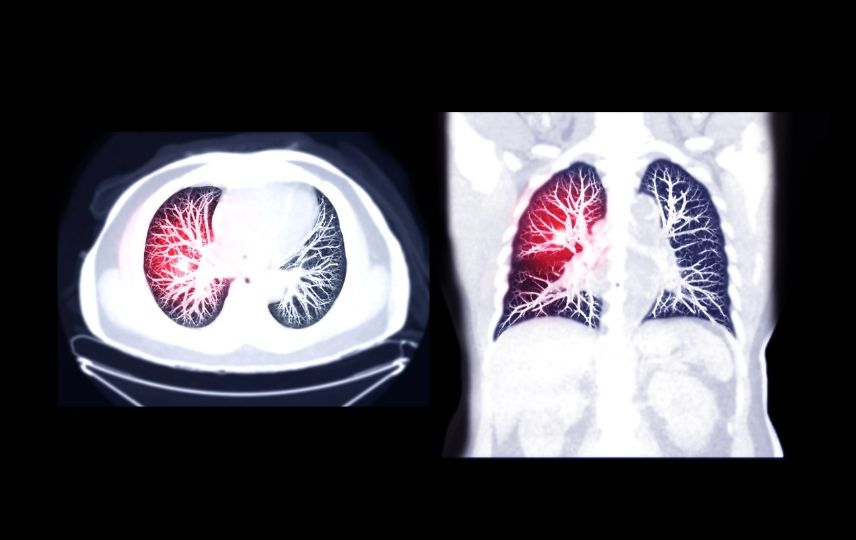

Pulmoner emboli nasıl tespit edilir?

Pulmoner emboli genellikle aşağıdaki testlerle tespit edilir:

- Bilgisayarlı tomografi (CT) taraması.